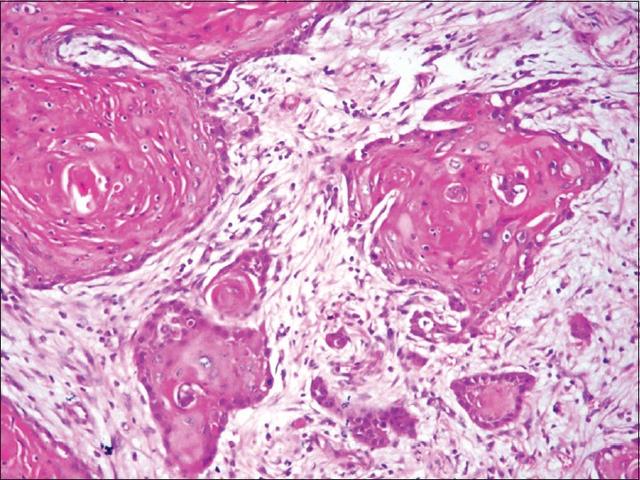

舌头良性肿瘤图片,舌癌和溃疡的区别

舌癌早期症状图片

舌癌早期症状20种图片

舌癌的图片大全 早期

舌癌早期10种症状图片

舌癌早期图片什么样子

舌癌的典型症状图片